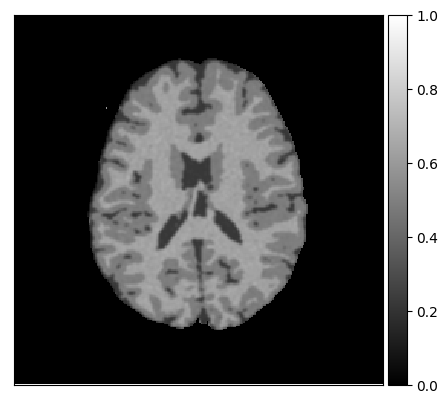

To be able to provide a proof of principle, we simulated different MR acquisitions from various anatomical models of the human brain [35, 27], using an MRI simulator (SIMRI [25, 26, 27]). The anatomical models consist of transverse slices of 20 normal brains and are publicly available through Brainweb333http://www.bic.mni.mcgill.ca/brainweb/. These models were used as input for the MRI simulator. For the experiments, we simulated two acquisition types: Brainweb1.5T, a standard gradient-echo acquisition protocol for a 1.5 Tesla scanner (c.f. [36]), and Brainweb3.0T, a standard gradient-echo protocol for a 3.0 Tesla scanner (c.f. [28]). Table 1 describes the parameters used for the simulation: magnetic field strength (B0), flip angle (), repetition time (TR), echo time (TE). Magnetic field inhomogeneities and voxel inhomogeneity (partial volume effects) were not included in the simulation.

Appendix A describes the nuclear magnetic resonance (NMR) relaxation times for the tissues in the Brainweb anatomical models, for 1.5 and 3.0 Tesla field strengths. The tissues in the anatomical models are grouped into ”background” (BKG), ”cerebrospinal fluid” (CSF), ”gray matter” (GM), and ”white matter” (WM) to compose the ground truth segmentation labels for the simulated scans. The simulations result in images of 256 by 256 pixels, with a 1.0x1.0mm resolution. Figures 5(a) and 5(b) show examples of the Brainweb1.5T and Brainweb3.0T scan of the same subject. For all scans, we used a brain mask to strip the skull.

In order to test the proposed method on real data, we use the publicly available training data (5 subjects) from the MRBrainS challenge444http://mrbrains13.isi.uu.nl/Figure. The acquisition parameters used for simulating the Brainweb3.0T are based on the MRBrainS acquisition protocol (3.0T scanner, gradient-echo, B0 = 3.0T, = flip angle, TE = 4.5ms, and TR = 7.9ms). Figure 5(c) shows an example of an MRBrainS scan. Again, a brain mask is used to strip the skull.